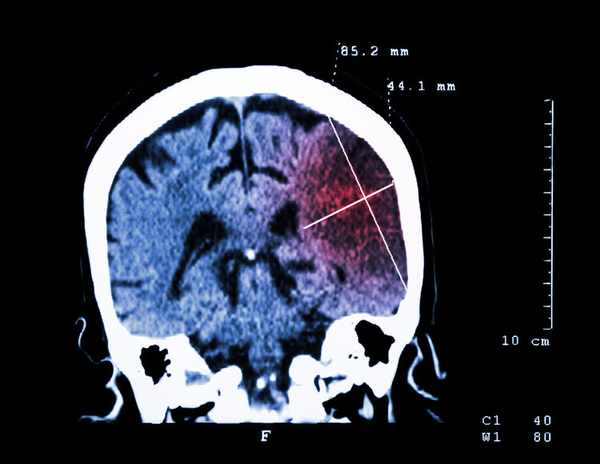

相關資料顯示,中國每年腦梗新發病例約200萬~250萬,死亡病例達150萬。尤其是青壯年死亡率占比明顯上升,達到14%,嚴重危害到我國人民生命安全。

二、腦梗致死、致殘率高,急救要抓住黃金時間

當腦梗發生,必須是"爭分奪秒",因為只要血液停止供應的那一瞬間,6s內人體神經細胞代謝就會受到影響,10-15s意識便可喪失,2min內腦電便失去了活動,5min腦細胞便會發生不可逆的損害,之後每耽擱1min,腦細胞就會死亡190萬個,最終直接危及到患者的生命。

所以發病後,及時抓住黃金救治時間非常重要。

一般來說,腦梗的黃金救援時間是3~4.5小時!患者是死、是殘,還是站起來的關鍵在此,如果在這個時間段內,可以及時送醫進行溶栓或取栓治療,那麼大部分患者都可獲得有效的治療,甚至治癒。